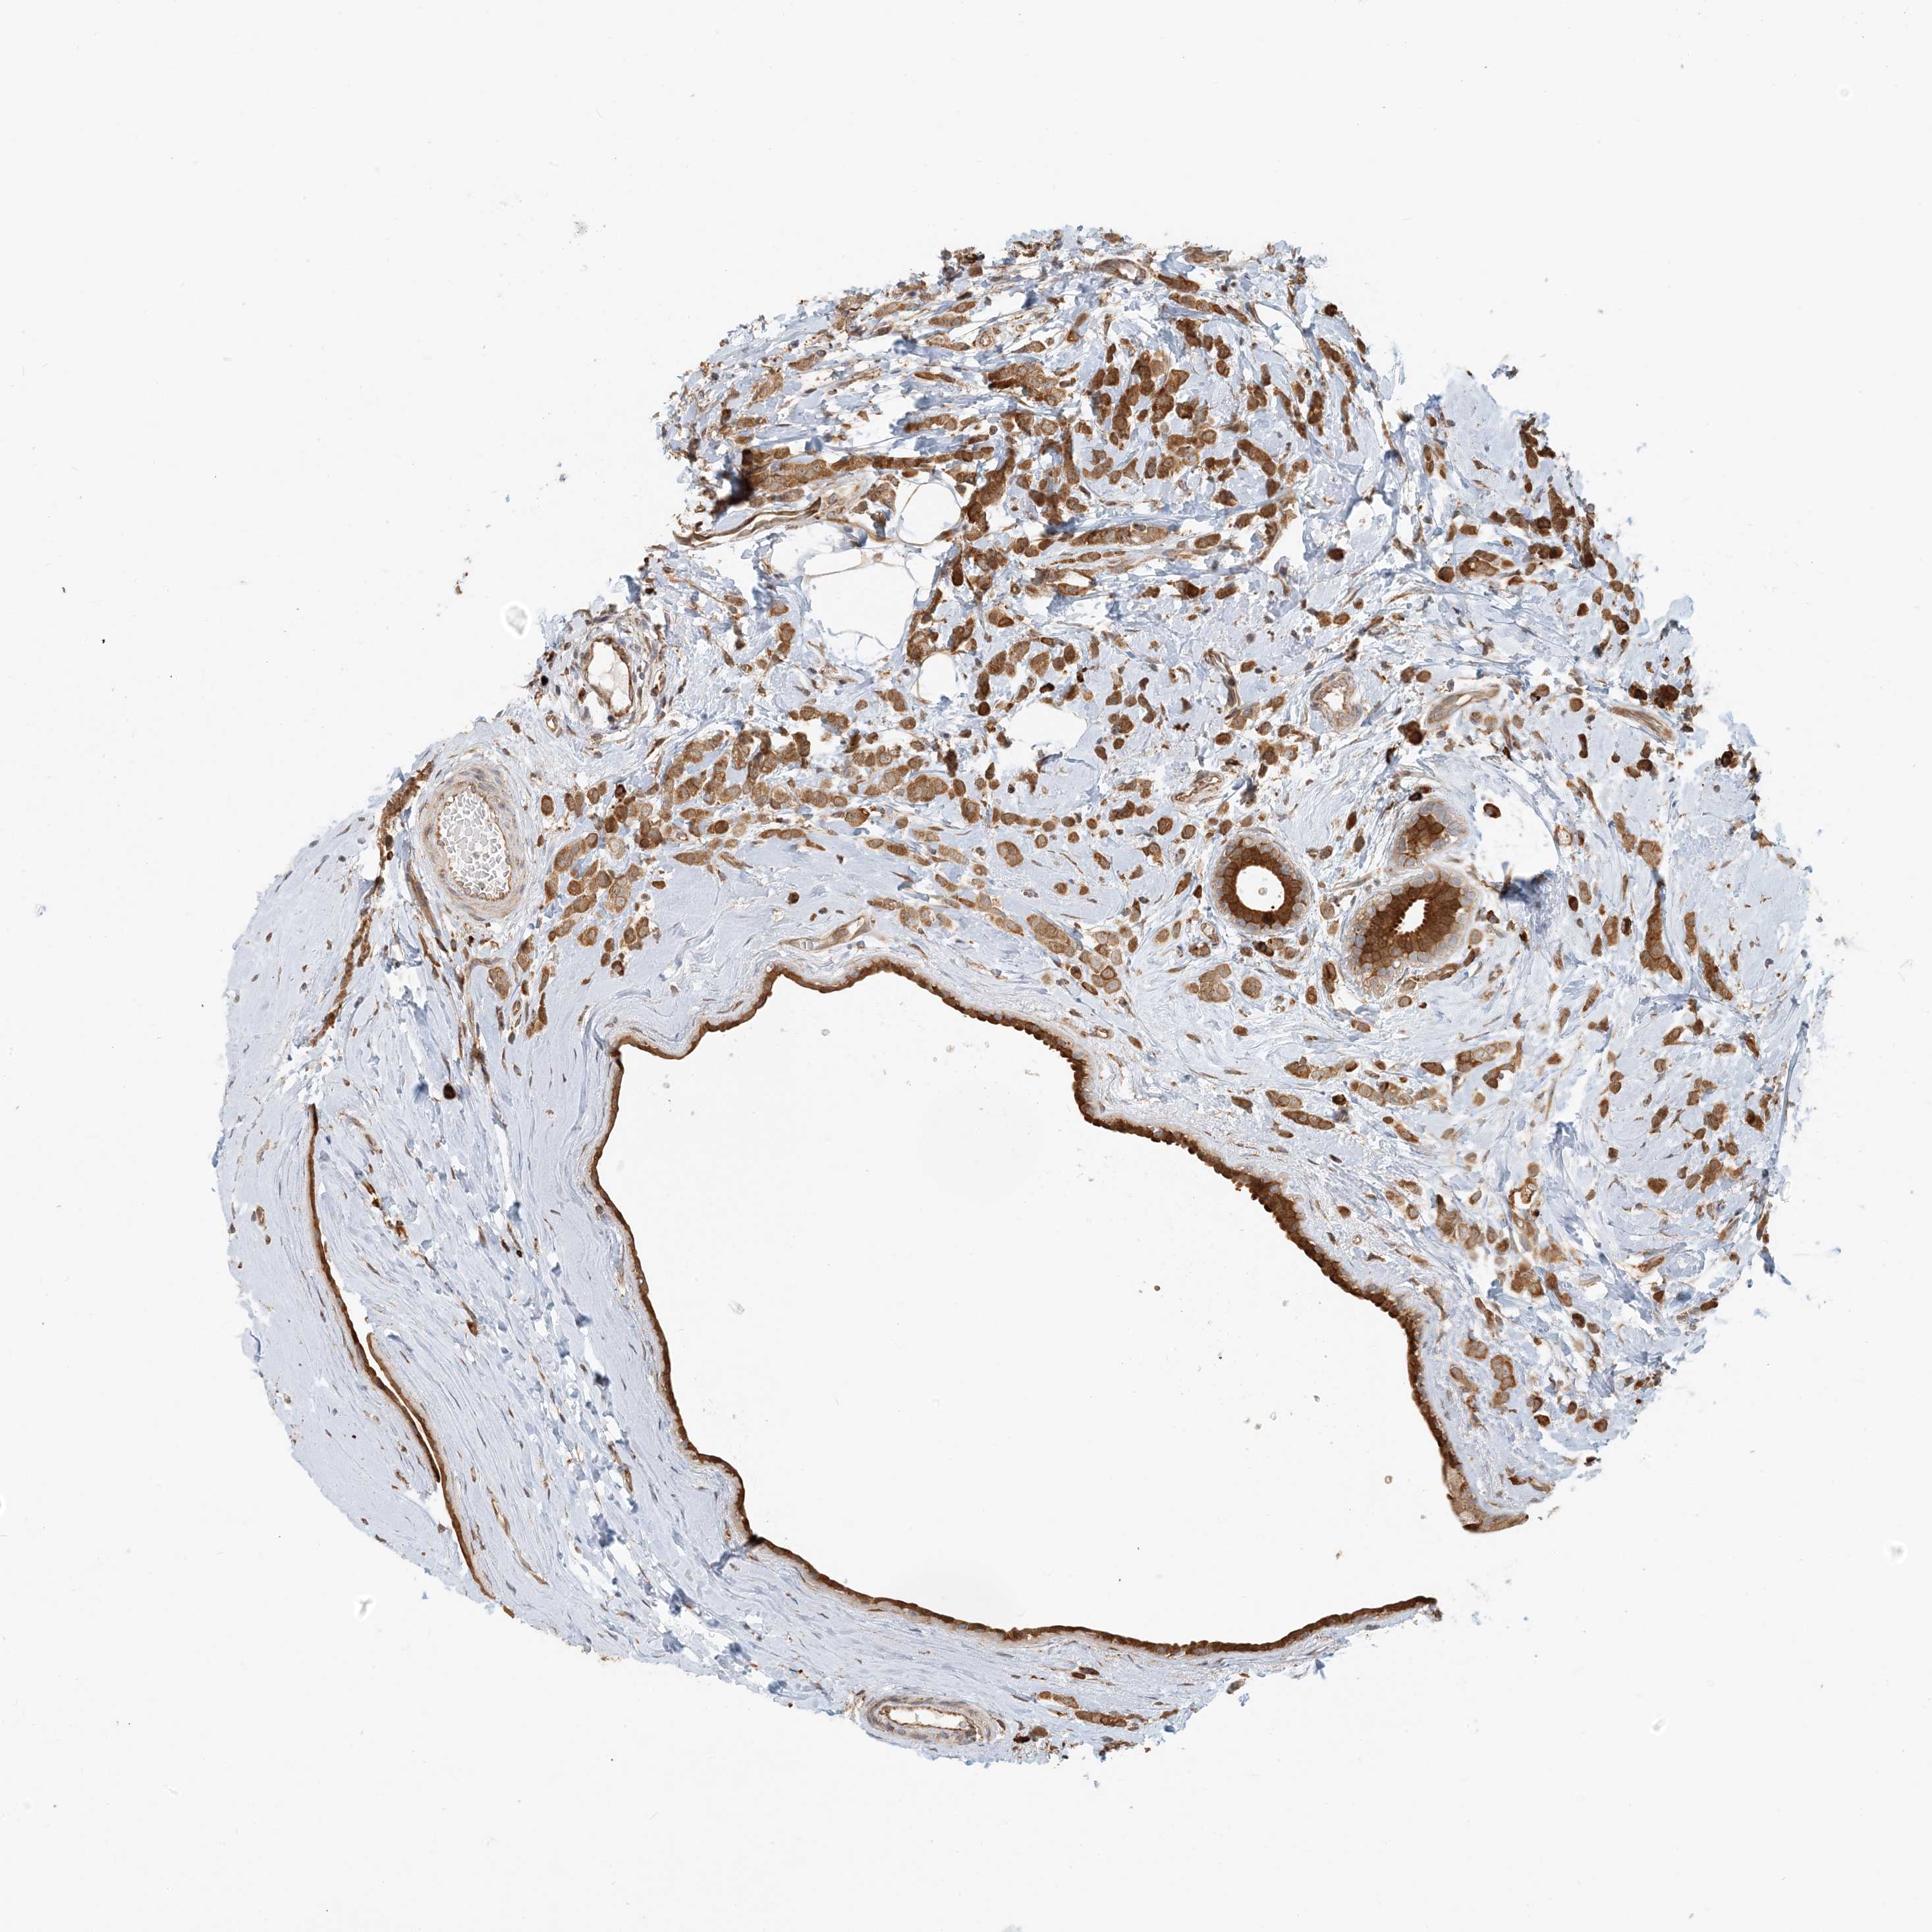

BRCA TCGA BRCA VALIDATION PROTEIN EXPRESSION

ANTIBODIES

AND

VALIDATION